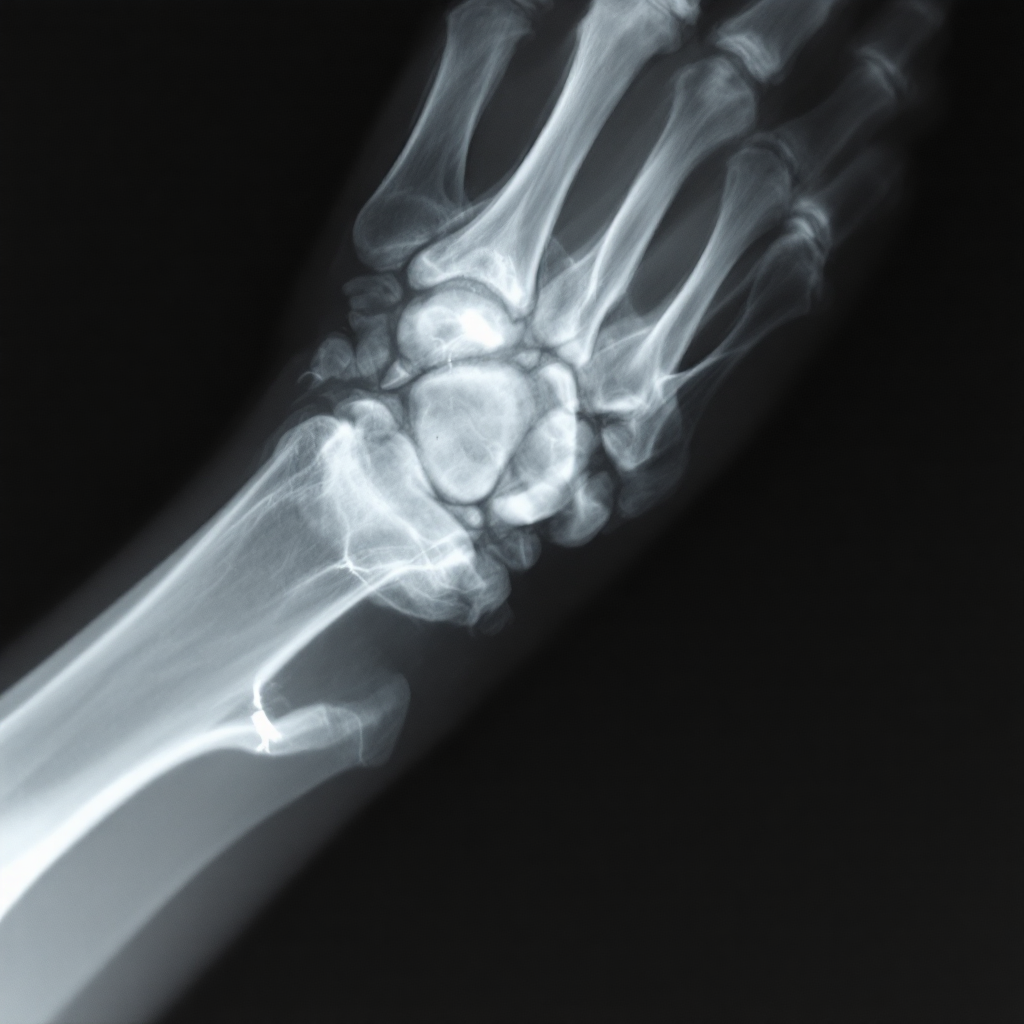

먼저 가장 기본적인 진단 도구는 엑스레이(X-ray)예요. 엑스레이를 통해 뼈에 금이 갔는지, 골절이 어느 정도인지, 뼈가 어긋나 있는지를 확인할 수 있어요. 특히 골절 선의 위치나 파편 여부도 판단할 수 있기 때문에 진단의 첫 단계로 꼭 필요해요.

엑스레이로는 골절이 명확히 보이지 않는 경우도 있어요. 이런 때는 CT(컴퓨터 단층촬영)나 MRI를 활용하게 돼요. 특히 관절 가까운 부분이나 미세 골절, 연골 손상 여부까지 확인할 수 있어서 더 정밀한 진단이 가능해요.